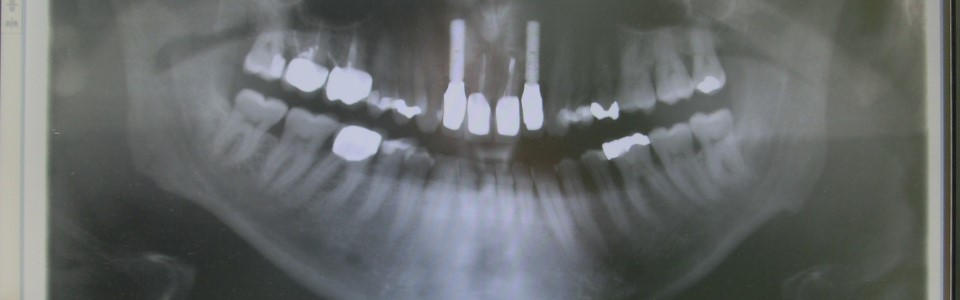

…für die punktgenaue Behandlung Ihrer Schmerzen Das digitale Röntgen zählt zu den fortschrittlichen bildgebenen Verfahren. Es bietet eine hohe Genauigkeit bei sehr niedriger Strahlenbelastung für den Patienten. Wir haben die Möglichkeit je nach Indikation einzelne Zähne oder das gesamte Gebiss mit einer Panoramaschichtaufnahme darzustellen. Das Bild ist sofort anzeigefertig auf dem Monitor. Man kann damit sofort, intraoperativ den OP-Verlauf von Implantaten kontrollieren. Das digitale Zahnröntgen ist unverzichtbar für die Diagnose, Therapie und Verlaufskontrolle über Erkrankungen der Mundhöhle. Karies, Knochenabbau durch Parodontose und Entzündungen an der Wurzelspitze können auf einem Monitor im Sprechzimmer dargestellt werden.